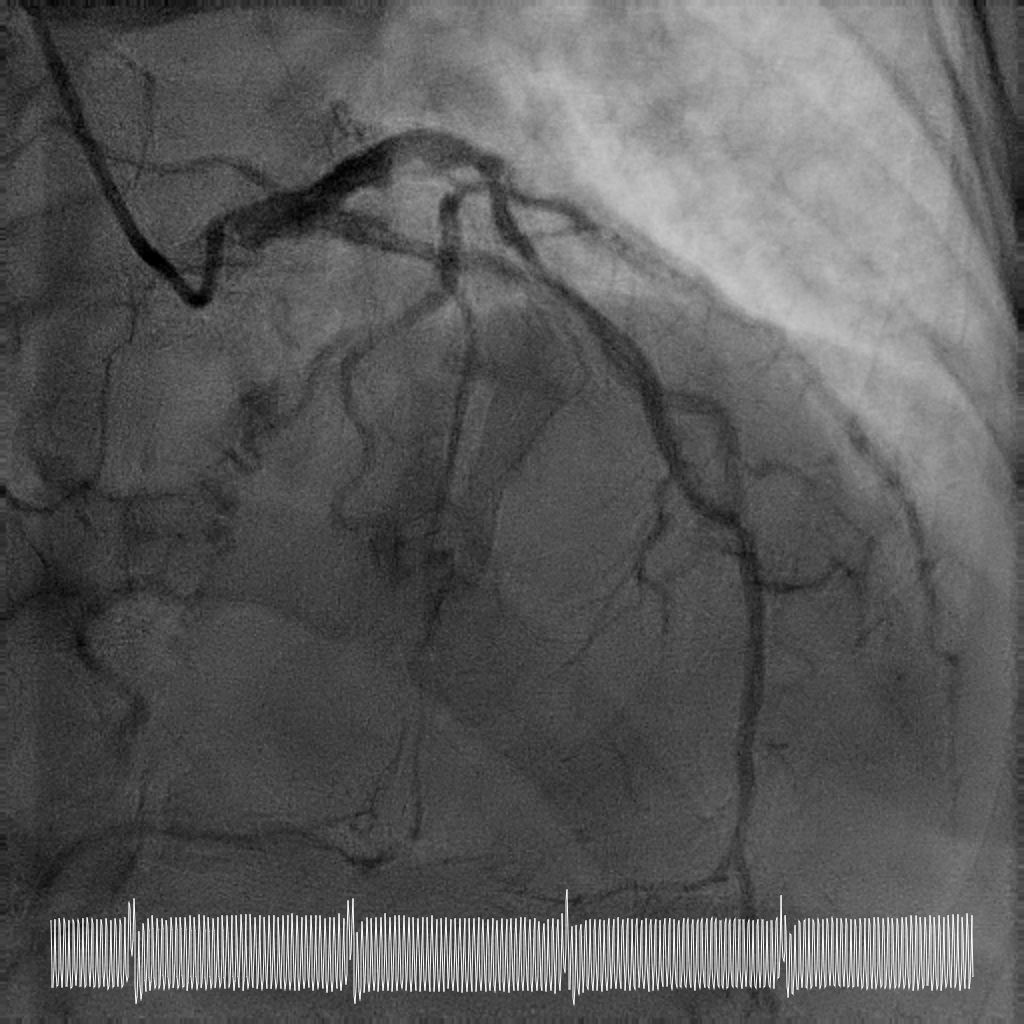

Rotational atherectomy with 1.5mm and then 2mm was performedfrom ostial LM to proximal LCx. Wiring of the LAD was only successful till midLAD with a separate distal LAD occlusion. LAD lesion was balloon uncrossableand half-way rotational atherectomy with 1.5mm burr. The distal LAD CTO wasthen crossed and balloon angioplasty undertaken. There was diffuse LAD disease, and the plan was then for ahybrid strategy. PCI to LM bifurcation was secured using the DK crushtechnique. 3.5x23mm Xience Sierra was placed in the LCx, 3.5x16mm Megatron inLM to proximal LAD followed by drug coated balloon angioplasty for the rest ofthe LAD with 2x40mm, 2.5x40mm, and 3x25mm balloon. She recovered well after her intervention and is infunctional New York Heart Association Class I, Canadian Cardiovascular Society Angina Grade 0. An elective angiogram was performed 6 months after indexprocedure to re-assess the results. This showed widely patient stents acrossthe LM-LAD-LCX, and excellent DCB results across the proximal to distal LAD andimprovement of her left ventricular ejection fraction.

This case illustrates the feasibility of a hybridrevascularisation strategy combining two-burr rotational atherectomy, left mainbifurcation stenting with DK crush, and downstream drug-coated balloonangioplasty in a patient with prohibitive surgical risk. Careful lesionpreparation and strategic device selection resulted in sustained long-termvessel patency and recovery of ventricular function in a patient with extreme-riskanatomy.